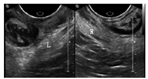

(1)仪器:采用Philips IU Elite彩色多普勒超声诊断仪,配备经腔内三维容积探头3D9-3v,频率3~9 MHz,探头二维发射角度130°,实时三维扫查角度85°。(2)方法:嘱受检者排空直肠,适当排空膀胱(残余尿量<50 ml),取膀胱截石位。在腔内三维容积探头上套一次性无菌探头套,再涂一层耦合剂。紧贴受检者会阴部,控制力度在静息状态时耻骨联合下缘距体表<1 cm,清晰显示盆底的标准正中矢状切面(包括耻骨联合、尿道、膀胱颈、阴道、直肠、肛管及肛直肠角),因为二维图像的清晰度决定三维图像的质量。将耻骨联合后下缘水平线设为参考线,观察静息及最大Valsalva状态时,宫颈最低点与参考线的距离变化。启用三维渲染模式,获取肛提肌裂孔标准切面(使耻骨联合后下缘、尿道、肛管始终在同一平面显示),分别在静息及最大Valsalva状态时,沿肛提肌内侧缘测量裂孔前后径、左右径、面积。所有参数均测量3次,取最大值为研究所用。(3)子宫脱垂的超声量化指标:目前无统一定论。通常在最大Valsalva动作时,以宫颈外口最低点为标记,测量宫颈外口最低点与参考线的垂直距离。分为三度,轻度:宫颈最低点位于参考线上<1 cm;中度:宫颈最低点位于参考线下方及下缘<2 cm;重度:宫颈最低点位于参考线下>2 cm[4]。(4)有效的Valsalva动作:嘱受检者深吸气后紧闭声门,用力往下作排气排便动作,时间持续>5 s,同时避免肛提肌共激活作用。此时,能动态观察到盆腔脏器向背尾侧移动,肛提肌裂孔逐渐增大。